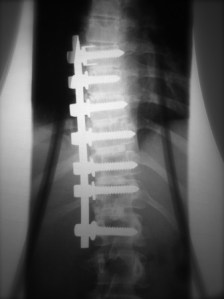

I step through the metal detector and, of course, it beeps. I don’t know what it is – perhaps my magnetic personality; or maybe the neurosurgeon left something behind, or implanted a microchip in my spine, but this happens to me about 2/3rds of the time I fly. I back up and step through again, another beep. After weighing the options of making me strip and expose my generous man-boobs to a horrified world, the guard has me step through one more time. Lucky for the world, one of the many rolls circumnavigating my waist shifts enough to cover my bionic vertebrae and the thing remains silent.